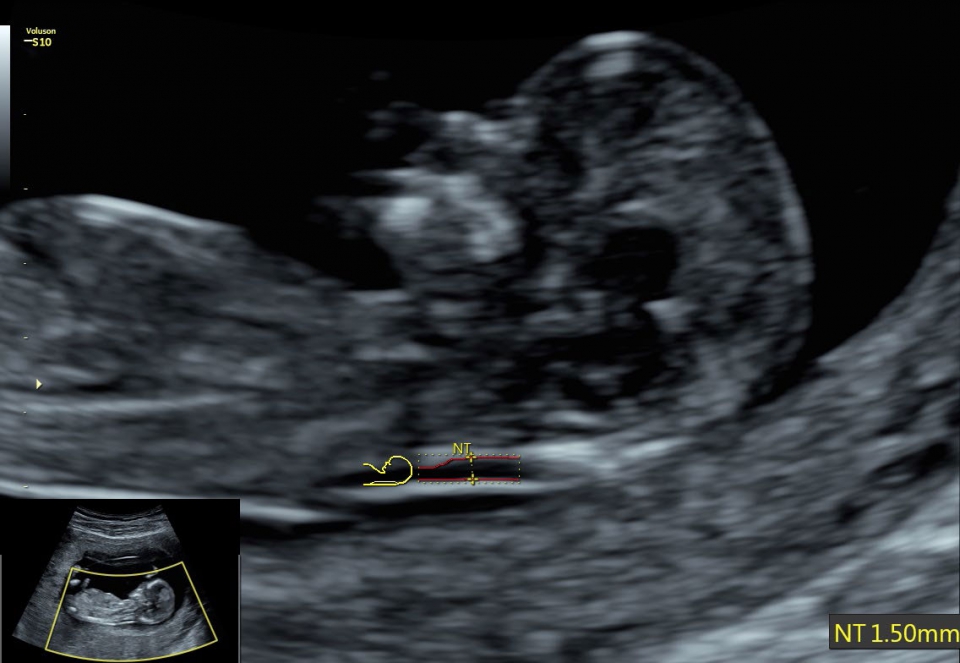

• SonoNT (Оценка воротникового пространства) и SonoIT (Оценка внутричерепного пространства): Эти технологии позволяют проводить полуавтоматическую оценку толщины воротникового пространства и размеров IV желудочка головного мозга плода в I триместре беременности. Они обеспечивают более точную оценку этих параметров с минимальными усилиями.

• Автоматический расчет толщины воротникового пространства SonoNT и размера четвертого желудочка SonoIT